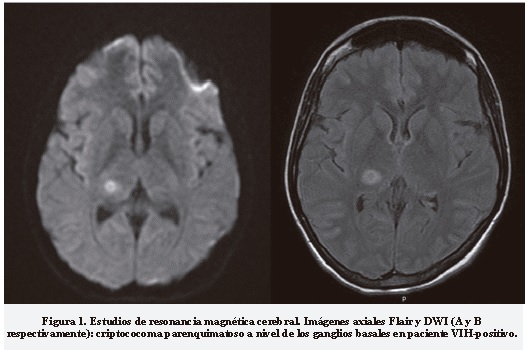

Mujer de 29 años, con antecedente de sida de dos años, mala adherencia al tratamiento antirretroviral; consultó por cuadro de tres días de cefalea, asociado a náuseas, diarrea y vértigo. Al examen neurológico se evidenció hemiparesia con piramidalismo. En RMC con contraste mostró criptococoma (Figura 1). La PL demostró hiperproteinorraquia, hipoglucorraquia, sin elevación de la presión de apertura, antígeno capsular para criptococo positivo. La paciente recibió manejo antimicótico estándar, presentó complicaciones por anfotericina B, como trombocitopenia e hipokalemia, además de colitis por citomegalovirus que requirió tratamiento con valganciclovir. Egresó sin secuelas de neuroinfección.

Se realizaron RMC al 87,5% (n = 7) en dos pacientes (28,6%) que fueron reportadas como normales, en el resto (71,4%) se encontró alguna anormalidad: en dos pacientes (28,6%) se halló hidrocefalia, de los cuales uno tenía cambios radiológicos compatibles con ventriculitis; en otros dos se evidenciaron criptococomas (28,6%) y de dos más (28,6%) se documentó trombosis de senos venosos a través de ARMC (Tabla 3).